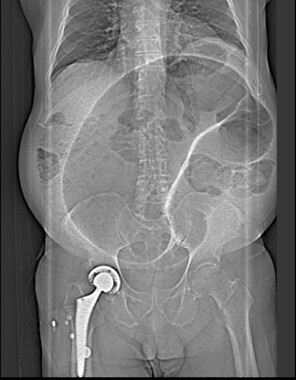

19-days following RALP the patient presented to the emergency department (ED) with a three-day history of obstipation, distension and reduced oral intake. Abdominopelvic CT revealed sigmoid volvulus (Figure 1). Flexible sigmoidoscopy confirmed sigmoid volvulus and decompression was performed with no complications. Two months after discharge, the patient presented again to ED with a similar three-day history of obstipation and progressive abdominal distension. Abdominopelvic CT and flexible sigmoidoscopy confirmed sigmoid volvulus again. One month later an elective anterior resection of the sigmoid colon was performed to prevent recurrence of symptoms following his urological procedure.